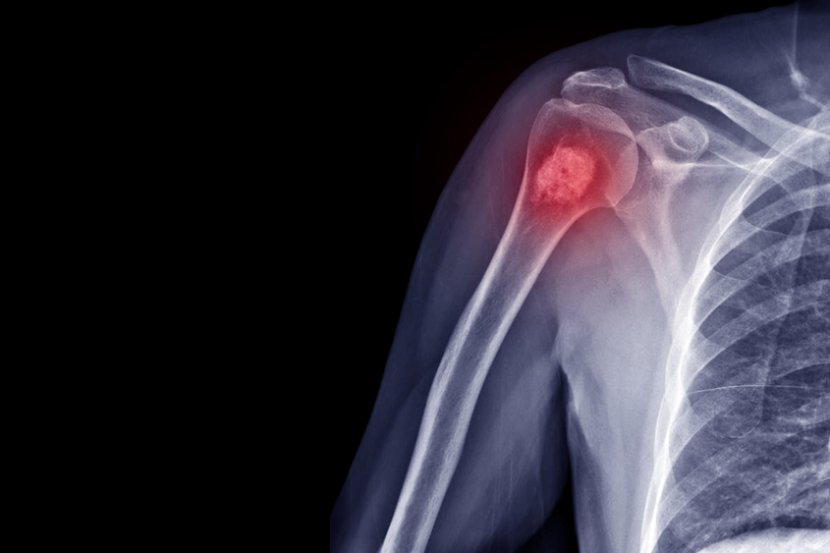

Nova dijagnostička tehnologija snimanja, koju su razvili istraživači sa California Institute of Technology nudi hirurzima mogućnost da naprave rezove 10 puta preciznije, omogućavajući im da sačuvaju čak 1.000 puta više zdravog tkiva i da pacijentima olakšaju oporavak. Tradicionalne metode, koje se koriste za određivanje da li komad kosti sadrži ćelije raka, oduzimaju mnogo vremena. Komad kosti se uklanja i šalje u laboratoriju gde se njen tvrdi kalcijum matriks polako rastvara, ostavljajući samo žive ćelije iza sebe. Preostali materijal se zatim iseče i slika. Budući da proces može da potraje između jednog i 7 dana, hirurzi se ne mogu osloniti na njega tokom operacije kako bi utvrdili zdravlje kosti oko i blizu tumora, pa će ukloniti čak i više nego što bi bilo potrebno - i više nego kada skidaju mekša tkiva, za koja se biopsijom mnogo brže ustanovljava koliko su kancerogena.

Nova tehnologija snimanja, nazvana ultraljubičasta fotoakustična mikroskopija 3D konturnog skeniranja u realnom vremenu ili UV-PAM, treba da zameni tradicionalni metod identifikacije kancerogenog koštanog tkiva. S obzirom na to da proces traje samo nekoliko minuta, on pruža hirurgu mogućnost da razlikuje zdravu kost od kancerogene kosti dok operiše.

UV-PAM koristi ultraljubičaste talasne dužine laserske svetlosti podešene da izazovu vibriranje molekula DNK i RNK. Imajući u vidu da su ćelije raka drugačije strukturirane, gušće spakovane i sadrže mnogo više DNK nego zdrave ćelije, oblast kancerogenog tkiva će apsorbovati više UV svetlosti i tako će obezbediti jači ultrazvučni signal od zdravog tkiva, što omogućava hirurgu da se jasno identifikuju delovi kostiju koje treba ukloniti.

- Možemo da dobijemo rezultate u roku od 11 minuta, tako da hirurzi znaju gde tačno da iseku kost - ističe profesor Wang i napominje da se trenutno ova nova tehnologija demonstrira samo u laboratorijskim uslovima i nada se da će uskoro početi da se koristi na pacijentima. Dotle će se, po rečima profesora Wanga, istraživači potruditi da još više ubrzaju snimanje i dobiju bolju rezoluciju snimka.